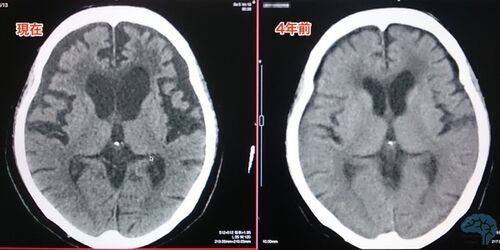

シチコリン2000mgの世界。

ご家族と相談しながら薬の可能性を追求している。緊張感は伴うものの、やりがいのある仕事である。 今回は、シチコリン2000mgで効果を実感出来た例をご紹介。